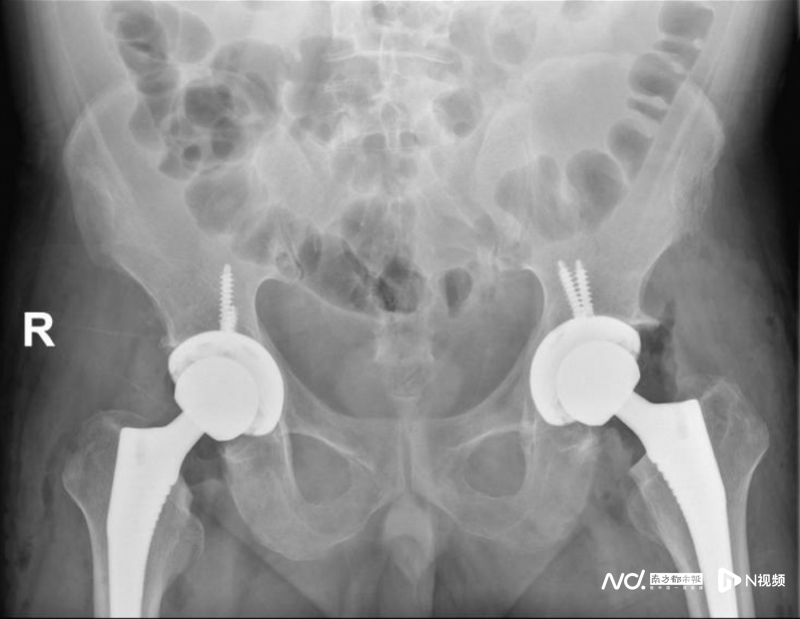

前不久,因病情加重致行走困難,影響日常生活,他才來到廣州和平骨科醫(yī)院骨科就診。經(jīng)過相關檢查后,確診為“雙側(cè)股骨頭缺血性壞死、雙髖關節(jié)退變、雙側(cè)髖關節(jié)半脫位”,需要進行雙側(cè)人工全髖關節(jié)置換。

術前影像檢查,患者的雙側(cè)股骨頭均已嚴重壞死。

不得不接受雙側(cè)人工全髖關節(jié)置換。